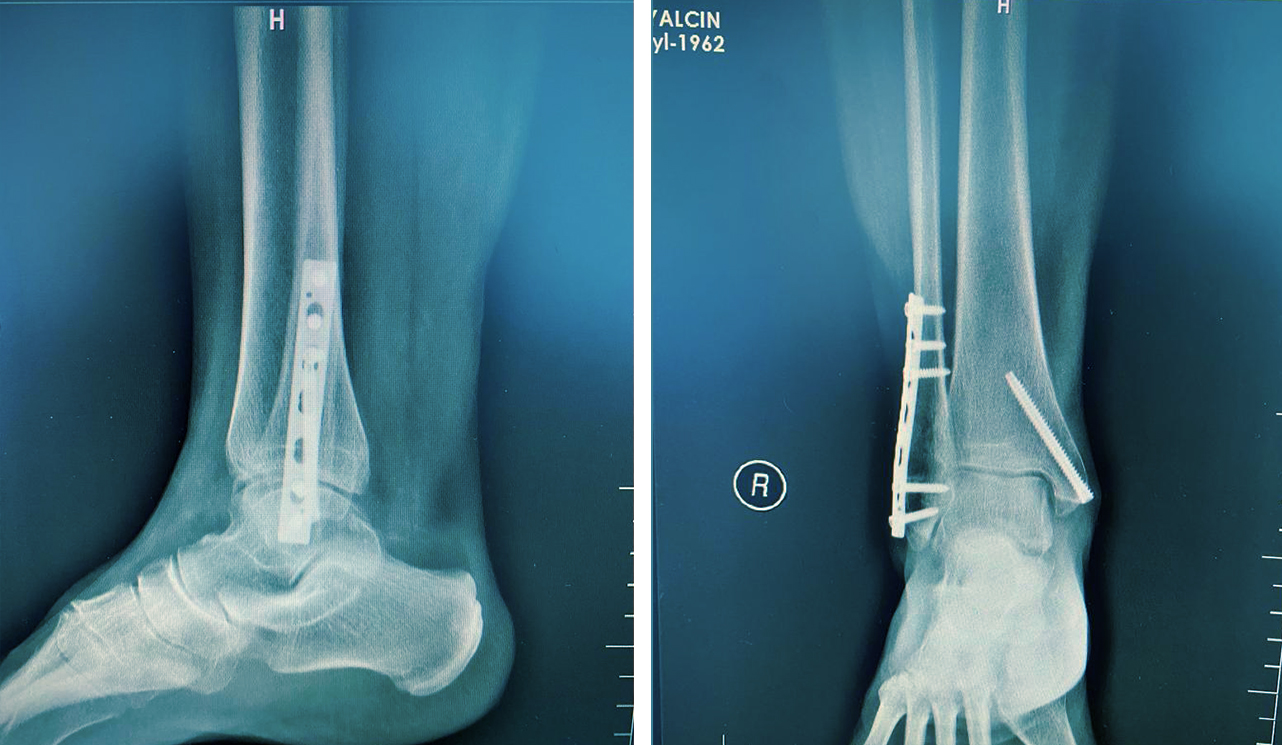

Ortopedik cerrahinin bir alt uzmanlığı olarak kabul edilir ve kırık kemiklerin tedavi edilmesine ve vücudun yaralı kısmının yaralanmadan önce sahip olduğu orijinal gücüne ve maksimum işlevine geri dönmesini sağlamaya odaklanır.